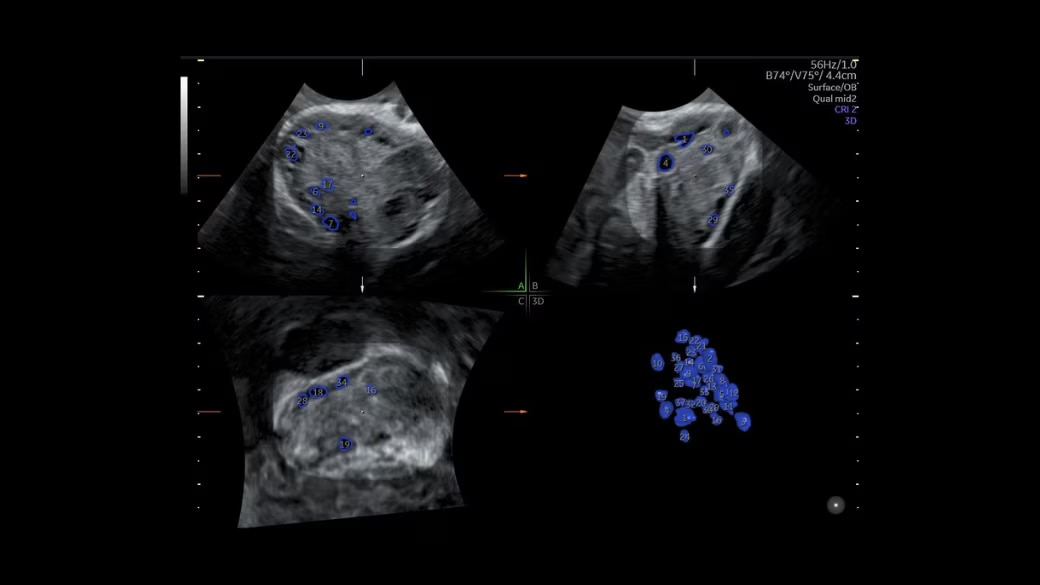

SonoAVC™ antral

Automate ovarian reserve assessment in 3D.

• Automatically counts antral follicles